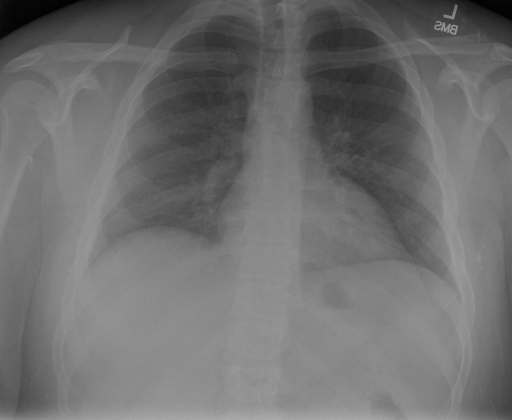

|X光影像|诊疗报告(医生)|XrayGLM|

|:-|:-|:-|

||根据X射线图像,心脏大小正常,肺部看起来很清晰。已经排除了肺炎、积液、水肿、气胸、腺病、结节或肿块的存在。该发现表明一切正常。换句话说,总体印象是胸部正常。|X光片显示,心脏大小正常。肺部没有气胸或胸腔积液的证据。骨骼结构看起来没有任何异常。总的来说,X光片表明没有发现急性心肺疾病的迹象。|